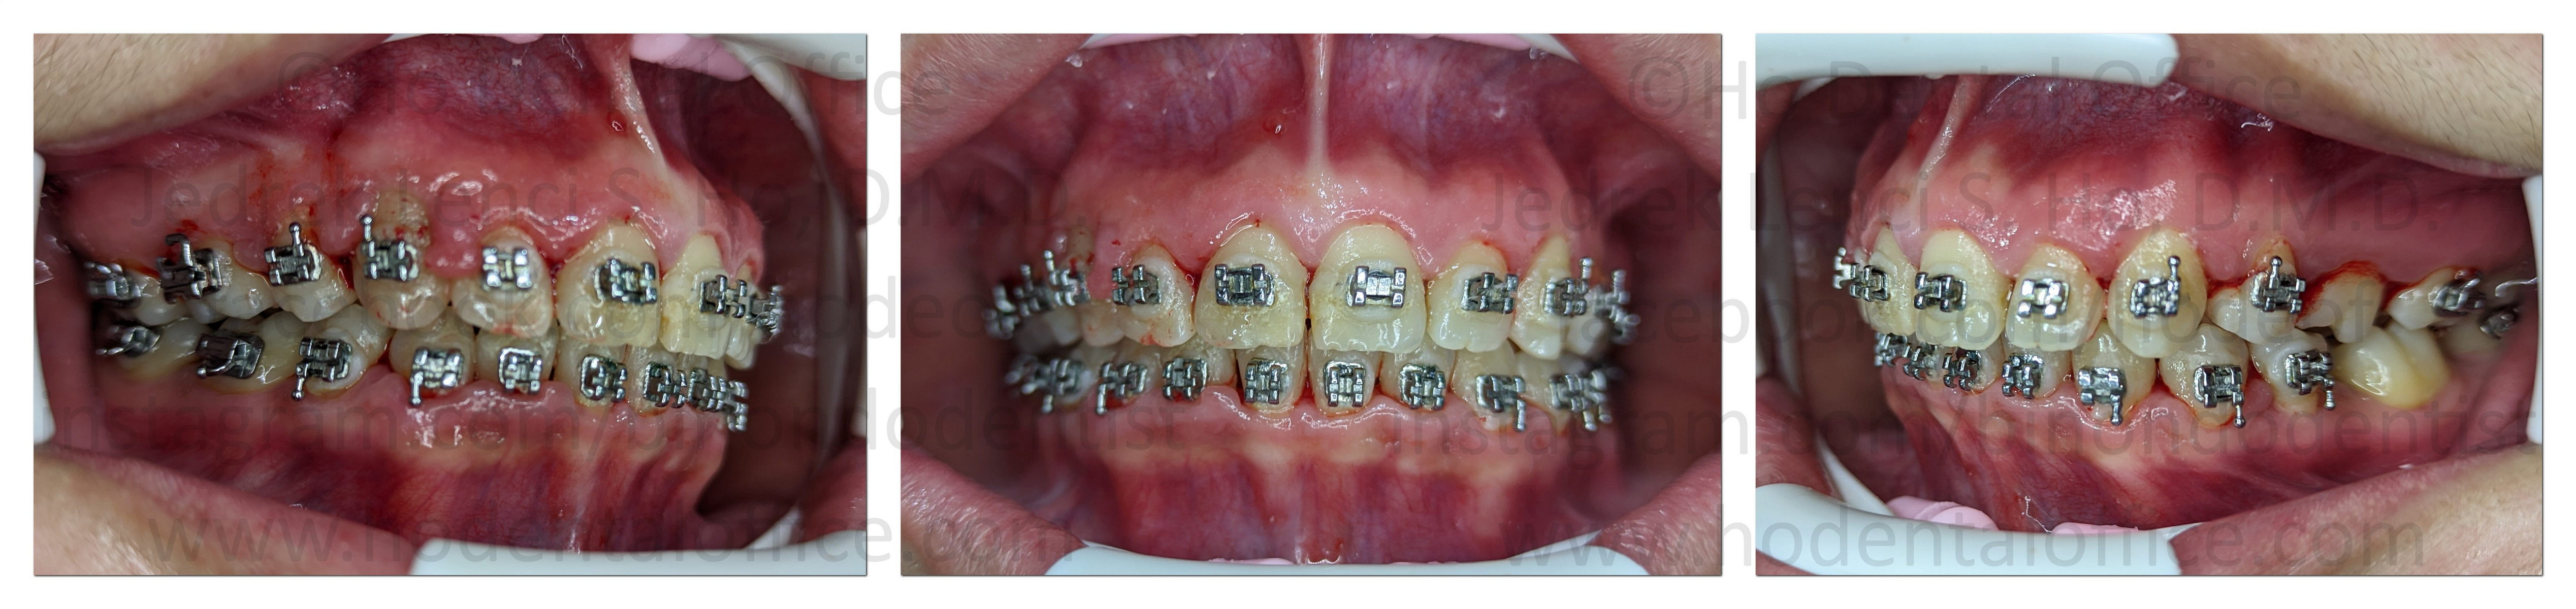

This gingival enlargement patient was being treated orthodontically when the pandemic struck. The patient missed a lot of dental appointments in the span of 2 years, and was unable to clean her teeth intensively, as a result, some of her gums grew larger due to inflammation.

The patient was next seen on July 2022. Notice that the gums grew larger and more apparent on the upper canine and incisor areas, this is due to irritation from the orthodontic wires and braces. A decision was made to perform gingivectomy using electrosurgery for her next dental appointment.